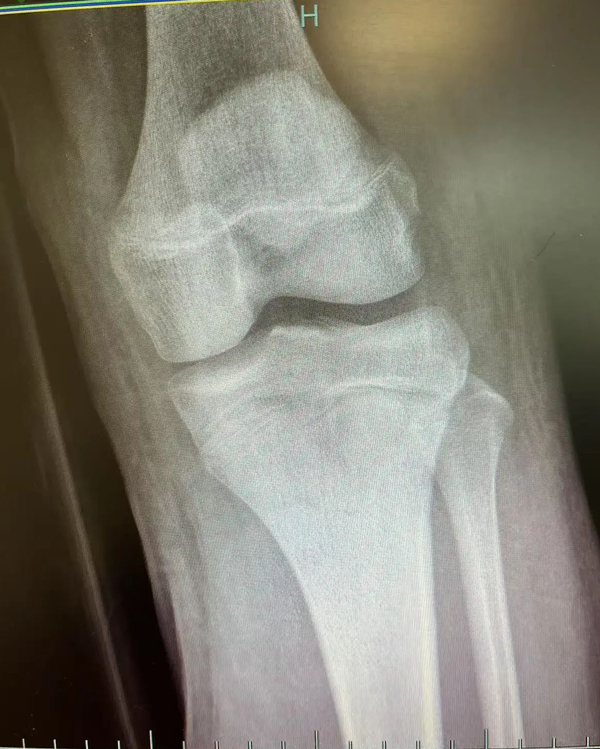

复位前

复位后

进修期间,一段特殊的经历让李刚感触颇深。2月底,一名女性患者因摔伤致左前臂肿痛伴活动受限被送入富阳骨伤医院。通过交流,李刚发现患者竟是家乡同胞,立即用方言安抚其情绪,这位老乡告诉李刚,自己在杭州工作,这次摔伤后先去了别的医院,给出的治疗方案是手术治疗,但听闻富阳中医骨伤医院的中医正骨技术后,慕名而来。经专家团队评估,最终为该患者采用“张氏骨伤疗法”中的手法复位结合杉树皮夹板外固定技术,未开刀便成功修复骨折。